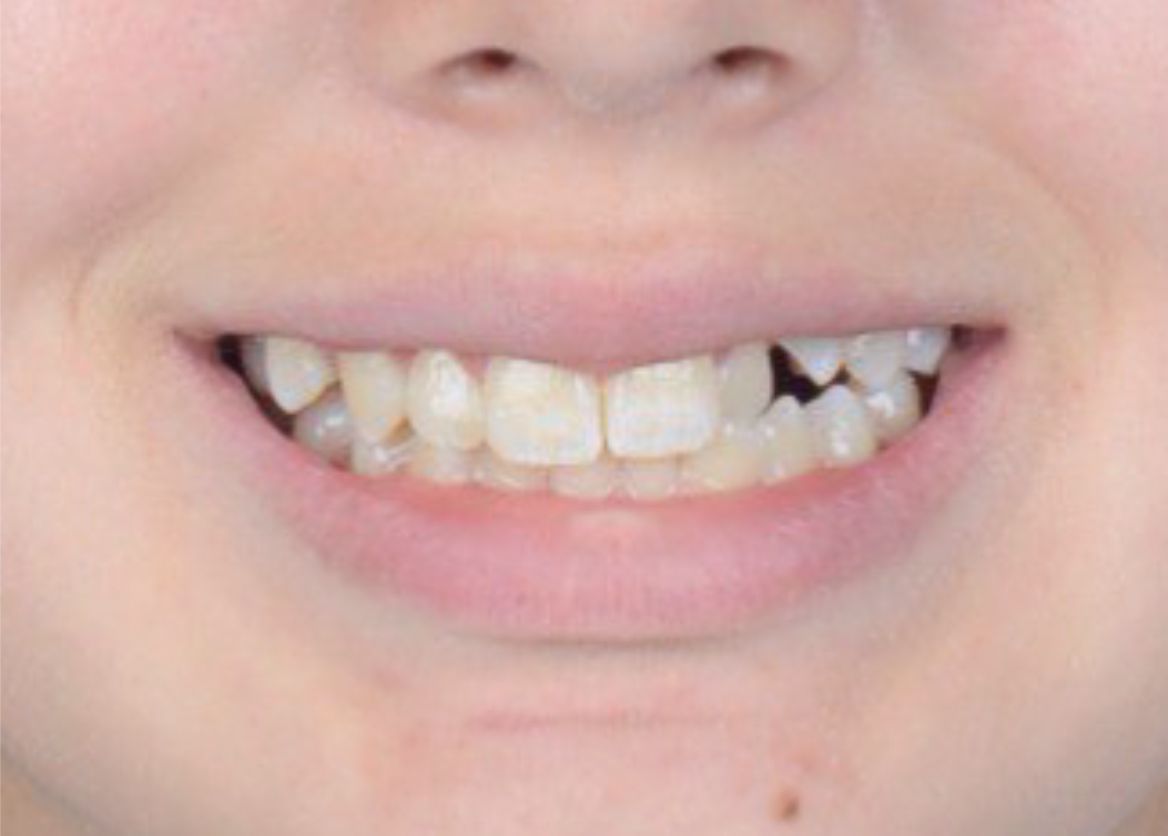

Исправить скученность зубов в зоне улыбки - было моей мечтой! Спасибо клинике ОК и Анастасии Андреевне за воплощение моей мечты в реальность!

Стеснялась улыбаться, потому что один зуб был как будто спрятан назад и казалось, что его нет. Сейчас я счастлива, что могу уверенно улыбаться и моя улыбка мне нравится!

Мне не нравилась моя улыбка и я постоянно испытывала смущение. Очень рада, что решилась на ортодонтическое лечение!

Не нравились мои кривые зубы! Настоящее чудо, что оказалось, что все можно изменить !!